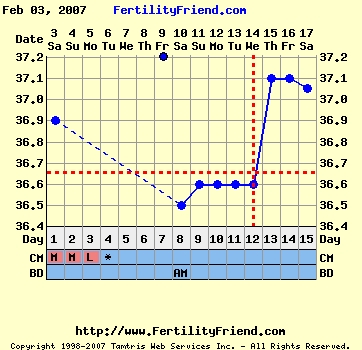

no ferty betette a pé-t 12. napra, circle is áttette ma oda, megjött az esze

Hát ha eddig nem volt magas hőd a betegség miatt, akkor szerintem most sem attól ment fel, nem?

igazság szerint én sem tudom, hogy most a betegség miatt magas a hőm 3 napja, vagy tényleg pé volt

de napközben nem éreztem magam lázasnak kivéve tegnap, szóval gondolom pé